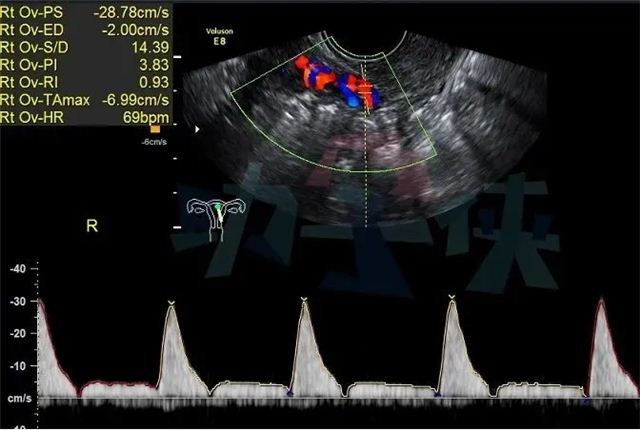

为什么需要进行子宫动脉的超声检查呢? 这个测量数值正常吗? 这个测量结果影响我怀孕吗? 怀孕后会影响宝宝生长发育吗? 这是许多孕妈妈或者备孕妈妈 经常问的问题, 今天超声科李琴医生和大家聊聊 子宫动脉的超声检查有必要吗? 为何要查子宫动脉? 子宫是孕育生命的摇篮,子宫动脉及其分支为它提供源料,输送营养,为胚胎发育做好准备。怀孕后,子宫动脉将富含营养物质的母血送至胎盘,与胎儿血液进行物质交换。子宫内膜如同种子发育的土壤,子宫动脉及其分支为摇篮和土壤提供源源不断的血供和营养,保证胚胎发育所需要的各种养分。 如何检查动脉血流? 检查时间尽量安排在排卵后的3-5天,也可以适当放宽到排卵后7天。这个时候最能反应胚胎着床时期的内膜血流情况,得到的数据往往最具参考意义。 目前也有观点认为检测时数据容易受到自身状态的影响,一次异常不具有参考性,尽量多次检测。 子宫动脉监测的意义 在孕前子宫动脉血流指数在月经周期的不同时段会有所不同,正常情况下,排卵后的黄体期也就是受精卵着床时期间子宫动脉的血流量增加,这对受精卵着床就非常有益。PI和RI值越低说明卵巢和子宫的血流灌注情况越好,胚胎着床率也就越高。如果子宫动脉血流异常,可能会导致胚胎发育不良,复发性流产,反复种植失败等。 子宫动脉血流并不仅仅在备孕前很重要,而且在怀孕时也非常的重要,因为它就是给子宫供血的。妊娠后,子宫动脉将富含营养物质的母血送到胎盘,跟胚胎的血液进行物质交换。如果子宫动脉异常会引起相应得很多疾病,如妊高症、胎儿宫内生长受限或羊水过少时,子宫动脉阻力不再呈现由高逐渐变低的下降趋势,甚至会有升高。 结果怎么看? 通过检查测量子宫动脉血流动力学的各种参数来了解子宫动脉供血情况,这些参数包括:血流阻力指数(RI)、搏动指数(PI)及收缩期峰值/舒张末期流速(S/D)这3个数值。 子宫动脉血流参数参考值: 在月经周期的不同时段,血流参数会有不同。比如在排卵后的黄体期(受精卵着床时期),子宫动脉血流量增加,对受精卵着床非常有益。此时子宫动脉由高阻低血流逐渐转变为低阻高血流状态,RI、PI和S/D值逐渐降低,舒张早期切迹变低至消失。此时的参数值一般以RI<0.85、PI<3、双侧S/D之和<12为准。 一旦确定怀孕,在孕早期内膜血流阻力会逐渐下降,舒张期早期切迹逐渐消失;此时的参考标准为:RI<0.85、PI<2.3、S/D两侧之和<12。 *目前临床上没有统一指南,以上参考数据仅供参考。 孕期正常子宫动脉血流参数参考值: 时期 早孕期 中孕期 晚孕期 RI <0.75 <0.73 <0.58 PI <2.25 <1.5 <0.82 S/D <6 <3.6 <2.6 不同病变的参数特征 *子宫动脉舒张早期切迹在孕 20 周后,随胎盘阻力降低而逐渐消失。若孕 26 周后,舒张早期切迹持续存在(箭头所示),可提示胎盘循环阻力增高,同时结合频谱 RI 异常能有效提高妊高症的检出率。 *患者若存在不孕症、胚胎发育不良、复发性流产、反复种植失败等病史时,可表现有子宫动脉血流阻力增高(表)。 表 不同病变黄体期子宫动脉血流参数 时期 不孕症 流产 RI >0.89 >0.85 PI >3.5 >2.5 S/D >8 >8 专家推荐 陈亚东 主治医师 超声科副主任 影像医学与核医学硕士研究生 专研肌肉、骨骼、关节以及关节辅助结构和邻近软组织,包括韧带、肌腱、滑囊、滑膜、神经、软骨等的肌骨超声诊断及超声引导下的穿刺活检、病理性囊液置管引流等的超声介入诊疗工作。曾获得中华医学会全国超声医学学术优秀论文;长治市科技进步奖应用类二等奖等。 李琴 副主任医师 擅长腹部、妇产科、血管及浅表等超声诊断,有着较丰富的经验。从事超声医学诊断工作已二十余年,曾在山西医科大学研修班学习,山西省人民医院进修,发表省级以上论文多篇。 供 稿丨李 琴 编 辑丨翟艳鹏 审 核丨雷 赫